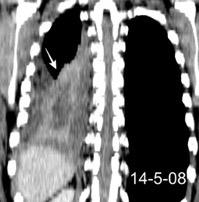

Marzo 2014: Perforación longitudinal distal secundaria a episodio de vómito (síndrome de Boerhaave). Derrame pleural izdo. que evoluciona a empiema.